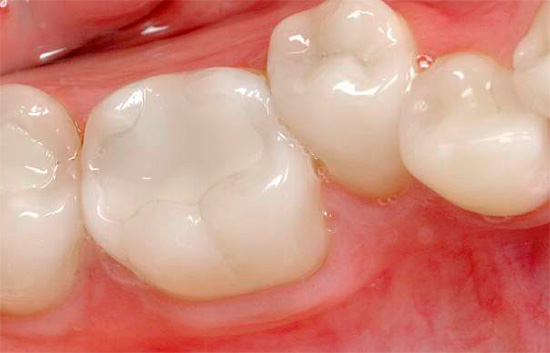

As clínicas modernas dão preferência a materiais de cura por luz funcionais e estéticos que se provaram no tratamento de cáries profundas. Eles são colocados em cavidades cariosas de qualquer classe, de uso conveniente, fácil e firmemente presos aos tecidos dos dentes e bastante duráveis com a execução exata dos detalhes técnicos da produção.

Infelizmente, cada empresa produz compostos com um conjunto de propriedades que podem ter aspectos positivos e negativos. O preço desses materiais também varia. Em qualquer caso, eles são indesejáveis para uso em cavidades profundas subgengivais, quando não há possibilidade de seu isolamento da umidade. Esse tratamento para cárie profunda pode não ser eficaz.